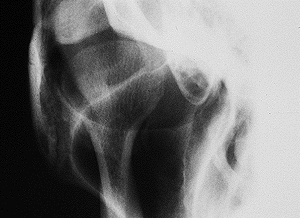

今度は、開口時(口を開けた状態)です。

関節頭(関節突起)と呼ばれる丸い突起の部分が、左の方に動いているのが見えるでしょうか?

これは、O-R法という撮影法です。眼窩(目の玉のあるところ)から、顎関節部を見ています。